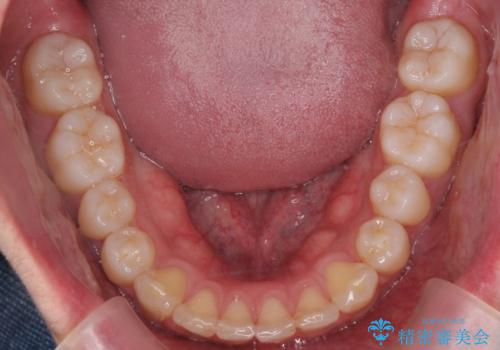

出っ歯の治療 インビザラインで抜歯矯正 親知らずを使用した矯正

- 出っ歯を主訴に来院。

上の小臼歯を2本抜歯しています。

そのかわり、上の親知らずを生かしており、歯の本数は減っていません。

矯正用ミニスクリューを使用しています(インプラント矯正)。

奥歯の歯ならびのずれが大きく、親知らずを抜いてすべて後ろに下げるか、手前の歯を抜いて前歯を下げるかの2択でした。

時間はかかりましたがしっかり前歯を下げて治療しています。